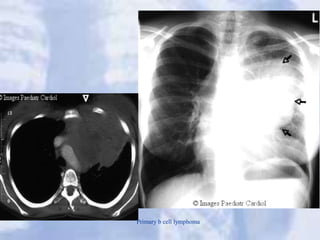

Perihilar mass: Hodgkin’s disease

Primary b cell lymphoma